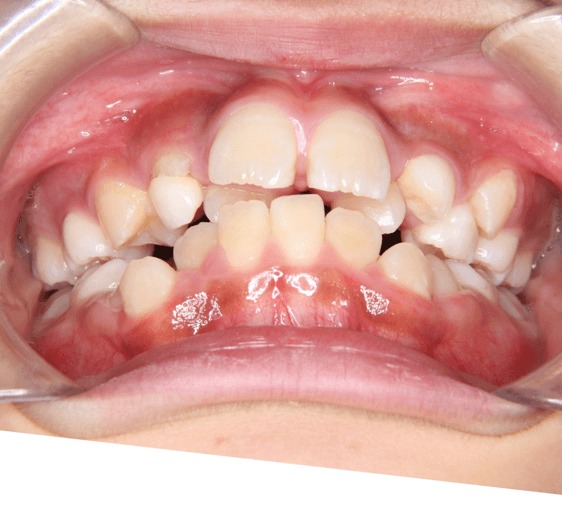

早期矯正治療 叢生症例①

主訴 | 歯の生えるスペース不足が懸念され、歯列の乱れ(叢生)を整えるために来院された患者様です。 |

---|---|

診断結果 | 7歳1か月の男児。 叢生の進行が見込まれると診断されました。 |

治療内容 |

|

治療後の経過 | 1年3か月の動的治療を通じて、上下顎の歯列が改善されました。 治療終了後は3〜4か月に一度の定期検診を継続しており、本格矯正治療の開始時期を判断していく方針です。 |

治療期間 | 動的治療期間:1年3か月 通院回数:11回 |

治療費用 | 420,000円(税別) |